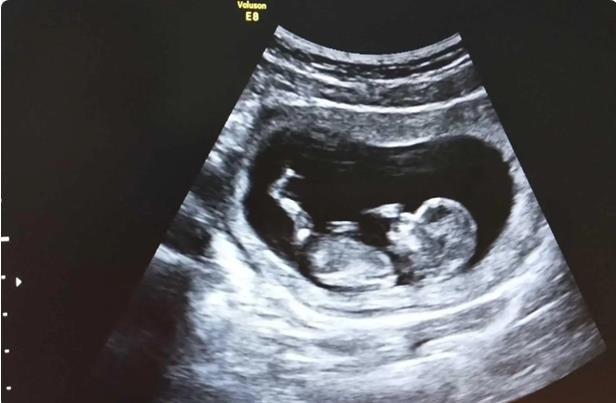

所谓的试管婴儿,不是将婴儿放到试管中长大。而是取出卵子,与精子结合并形成胚胎。当胚胎成活之后,转移到女性的子宫内,开始着床和妊娠。正常来说,女性怀孕过程中,卵子与精子会在输卵管碰撞到一起,并形成受精卵。而从体内取出来之后,需要有一个培育的媒介,试管便发挥这样的作用。了解恩施州中心医院能不能做试管婴儿,便可以着手去准备。